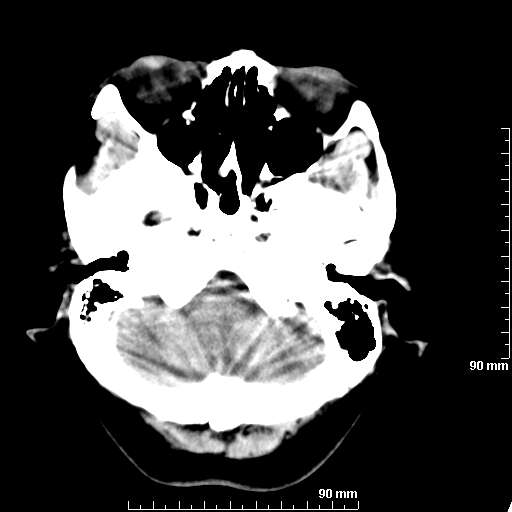

[维修案例解析] 大家猜猜看,这个伪影是怎样产生的.

二马日王 显示全部楼层 发表于 2011-6-9 18:12:55 |阅读模式

我院西门子单排CT由于一零件受损而产生的伪影.

哈哈,都不是。是虑线器fiter裂损。大家没想到吧。

哦,跟脑出血有点像哦

形状不规则,边缘模糊。比较特殊的一种伪影哈!

这种伪影很常见!伪影应该是在视野的中心的。

西门子的虑线器fiter裂损这才是很难见的问题,GE的最常见

虑线器老化,中间崩裂一块掉了

确实是虑线器,但是很少见

确实是虑线器,听说过,赞一个